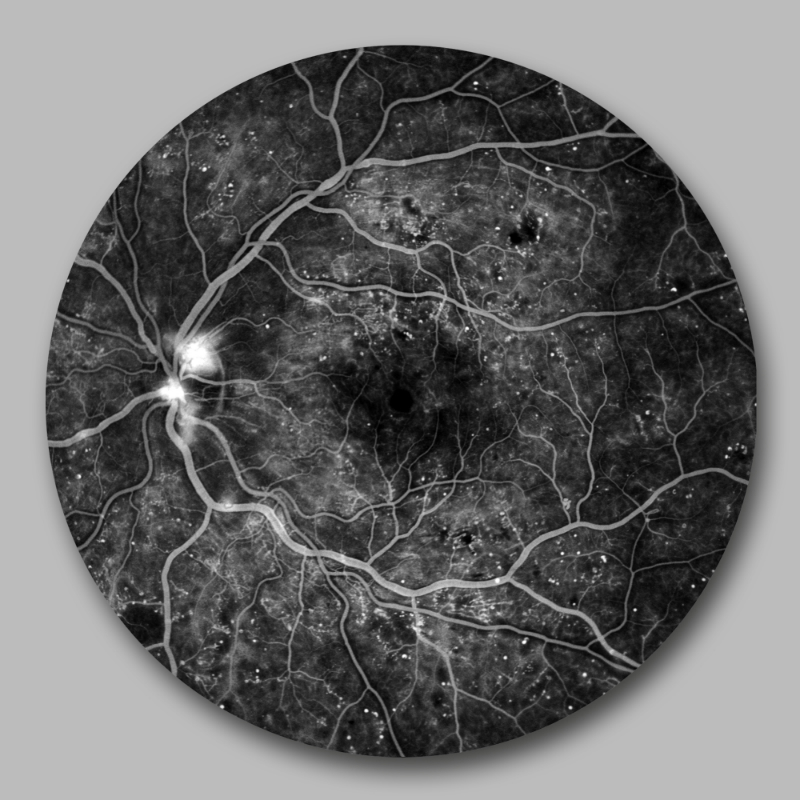

Die Netzhaut am Augenhintergrund ist die einzige Stelle des Körpers, an der man direkt auf die Blutgefäße schauen kann. Bei Diabetes kann es hier zu Gefäßaussackungen, Blutungen oder Flüssigkeitsaustritt kommen. Veränderungen können wir mittels Netzhautfotographie oder Fluoreszenzangiographie genauer untersuchen. Bei starken Netzhautveränderungen kann eine Behandlung mit intravitrealer Injektion oder Argon-Laser notwendig werden.